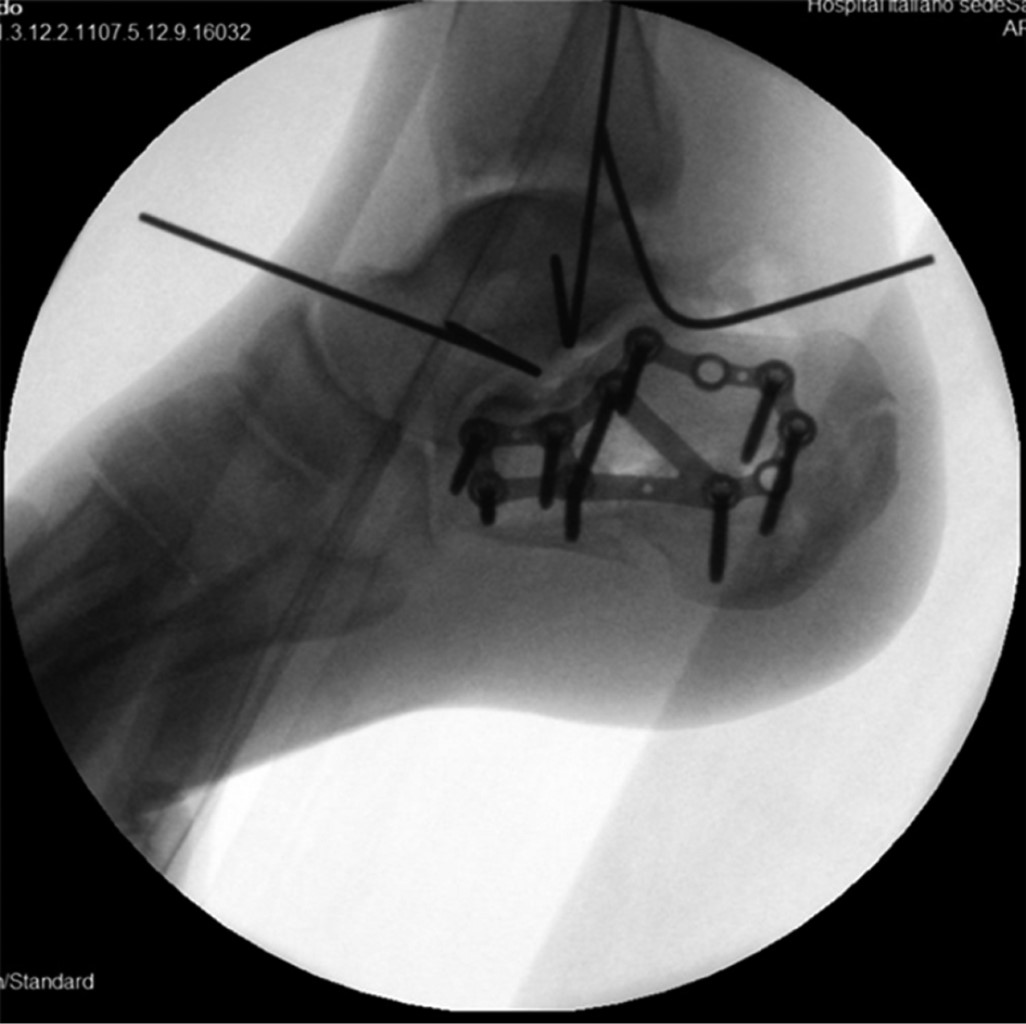

Se decidió realizar primero la reducción del calcáneo mediante clavijas y posteriormente osteosíntesis con placa para calcáneo SCP bloqueada de 3.5 mm (South American Implants, Argentina). Se constató adecuada reducción mediante el intensificador de imágenes (Figura 4). Aprovechando el mismo abordaje, se exploraron los ligamentos LPAA y LPC. Ambos presentaban signos de ruptura aguda, cercanos a su inserción proximal. Se realizó la reconstrucción ligamentaria utilizando anclajes con suturas transóseas al peroné distal. Se constató una adecuada estabilidad ante maniobras de estrés.

Figura 4